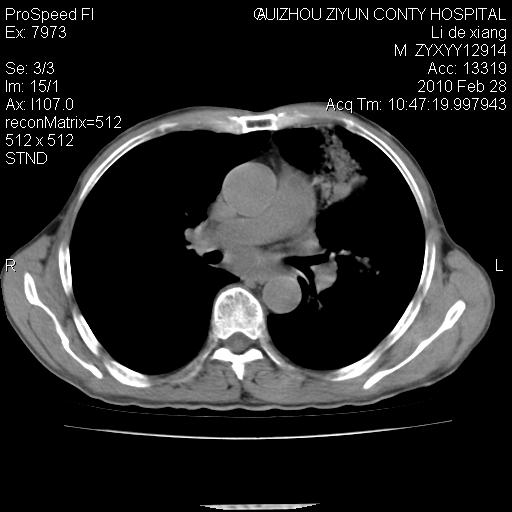

标题: CT24776:男 71Y 咳嗽咳痰胸痛两月,伴声音嘶哑。 [打印本页]

标题: CT24776:男 71Y 咳嗽咳痰胸痛两月,伴声音嘶哑。

左侧中央型肺癌伴左肺上叶阻塞性肺炎及节段性不张可能性大,建议纤支镜检查!

左侧中央型肺癌伴左肺上叶阻塞性肺炎及节段性不张可能性大,建议纤支镜检查!纵隔淋巴结转移.

左侧中央型肺癌伴左肺上叶阻塞性肺炎及纵隔淋巴结转移。

左肺门部肿块,伴左上肺斑块影,周边模糊,支持左肺中央型肺癌伴节段性不张及阻塞性肺炎,结合支气管镜检查。

患者有声音嘶哑,若时间长了,没改变,喉镜检查无异常,可考虑左侧喉返神经受累,因为:左侧喉返神经绕主动脉弓或肺动脉韧带的主动脉端,沿气管与食管之间的沟上行至颈部.

支持肺癌.

左上叶支气管狭窄,阻塞性病变,肺门肿块,纵隔及肺门淋巴结增大,中央性肺癌

左肺中央型肺癌并阻塞性改变、纵膈 淋巴结转移

左侧中央型肺癌伴左肺上叶阻塞性肺炎及纵隔淋巴结转移

支持 左肺中央型肺癌伴左肺上叶阻塞性肺炎,纵隔淋巴结转移。